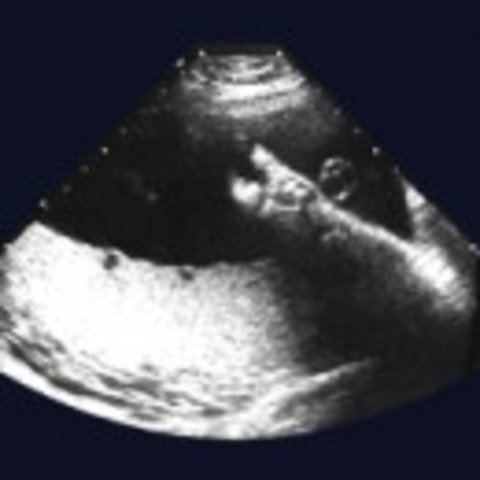

Your baby’s head will probably drop into your pelvis

Your baby will be getting into position ready for labour to start.

Contact hospital and have everything prepared for your baby's brith.

Your baby is born!